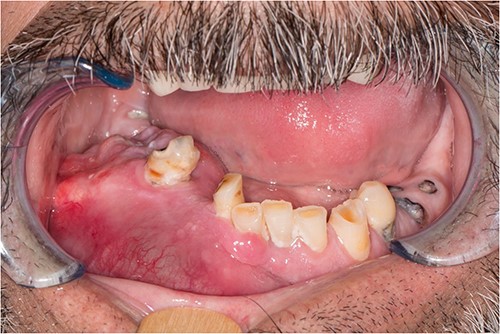

A 52-year-old male presented with a 4-month history of right lower lateral lip swelling and dental complaints. On physical examination, there was a large right mandibular mass with several floating teeth extending from the symphysis to the angle (Fig. 1). The patient’s history was notable for hypertension and a 36-pack year smoking history. He denied any other concerning symptoms. Computed tomography (CT, Fig. 2) imaging demonstrated at large heterogeneous, multiloculated, expansile lesion of the right mandible. An incisional biopsy was performed, and results demonstrated epithelial tumor islands with columnar cells exhibiting peripheral palisading, stellate reticulum-like areas, granular cells, and reverse polarization (Fig. 3). Following diagnostic confirmation of multicystic granular cell ameloblastoma, the patient underwent successful surgical resection and reconstruction. Final pathology showed a 5.0-cm granular type conventional multicystic ameloblastoma with negative surgical margins. At time of report, 7 years after resection, our patients is alive with no evidence of recurrence.

Physical examination revealing an evident large right mandibular lesion present in the patient.